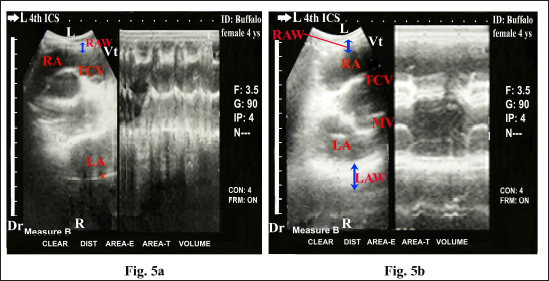

The heart was imaged from the left fourth ICS in midway between the elbow and shoulder points as the angle of the transducer directed dorsally and slightly cranially toward the third ICS, showing visualization of the right ventricular outflow tract (RVOT); RA, RV, TCV, PA, and pulmonary valve (PV) (Fig. 3). Cross sections at the apex of the heart, either in diastole (Fig. 4a) or systole status (Fig. 4b) showed RV and LV. Cross sections in the base of the heart showed RA, LA, TCV, and MV either in diastole (Fig. 5a) or systole status (Fig. 5b). Regular and strong myocardial contractility was clearly observed in both B-mode and m-mode 2-D-gray scale ultrasonography in all buffaloes.

Fig. 5. Echocardiogram in adult healthy female non-pregnant (4-year-old) buffalo (left side) during diastole (a) and systole (b) using a 3.5 MHz sector 2-D-gray scale transducer (B-mode and M-mode). It was imaged from the left fourth ICS in the midway between the elbow point and shoulder point. It showed CS in the base of the heart with regular and strong contractions and clear margins. The RA, LA, TCV, and MV were clearly imaged. Echocardiographic dimensions, either in diastole or in systole, were also visualized, including right atrial wall thickness (RAW) and left atrial wall thickness (LAW). Dr; Dorsal. Vt; Ventral. R; Right. L; Left.